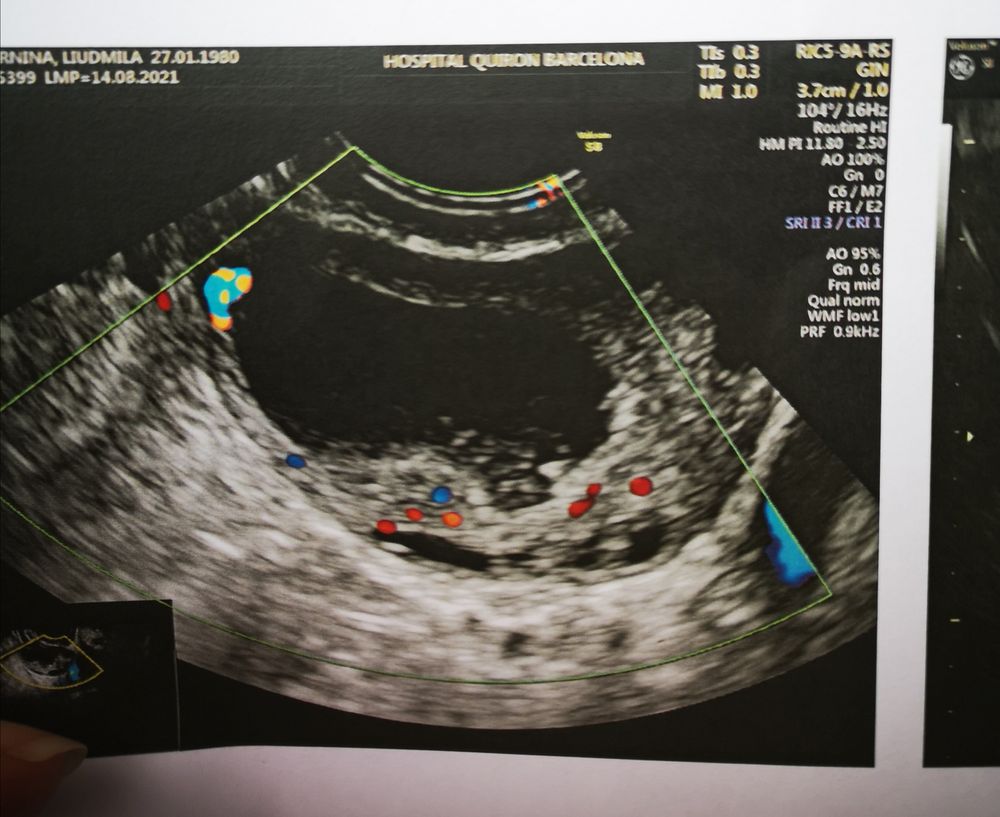

Жт или лютинизация фоликула?

Скоро два раза мама!!!))), ну у меня 1 дпо получается 20 мм. У меня лопаются 22-24 мм, на 4 дпо уже 26. Ну я так понимаю жт и лютинизированый фоликул трудно отличить. Надо сразу в день О смотреть. Просто на 1 дпо мне вообще левый врач смотрел.

Мила, у меня как-то в цикле стимуляции непонятки тоже были с УЗИ. В итоге пошла на экспертное УЗИ, дороговато конечно чем обычно, но хоть все по полочкам разложили. В итоге было 1 ЖТ, 1 лютеинизировавшийся фолликул и 1 в регресс ушел. По изображению лютеинизировавшийся фолликул и ЖТ очень похожи по мне, но врачи их как-то различают по кровотоку, содержимому и т.д.

Екатерина , жидкости нет, но сегодня по идее 4 дпо, ее уже и не будет. Но у меня еще не разу за полтора года планирования жидкость не видели и быдо 2 Б за это время.